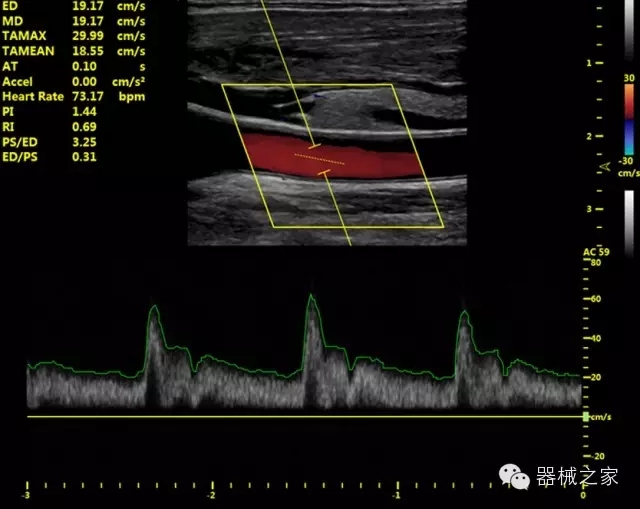

·獨有的HoloTM PW 實時3取樣門PW成像技術,精確進行血管診斷;

·一鍵優(yōu)化B、Color、PW,Auto Doppler自動識別血管位置、偏轉角度等,提高工作效率;

·30°超廣角精細偏轉成像技術,更優(yōu)異的頻譜圖像;